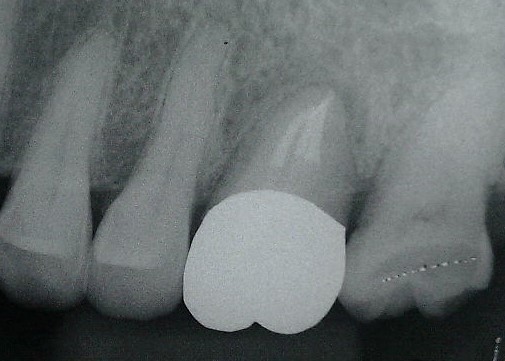

治療前

「大きな虫歯で残せないから抜いてインプラントだね」と言われ抜歯までされた方が、移植を希望して来院されました。

補綴後

数カ月経過観察後、状態も良くなってきたところで被せ物を入れました。

(X線より周りの骨も回復してきたのが分かる)